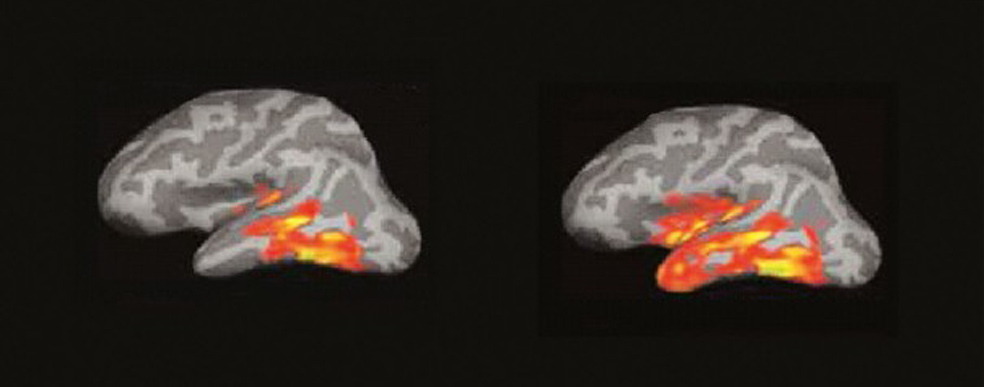

El cerebro del lector: un incendio de ideas

La imagen por resonancia magnética del cerebro de alguien que lee muestra algo parecido a un incendio forestal en un día de viento. Las pavesas vuelan y prenden nuevos conatos en diferentes zonas…